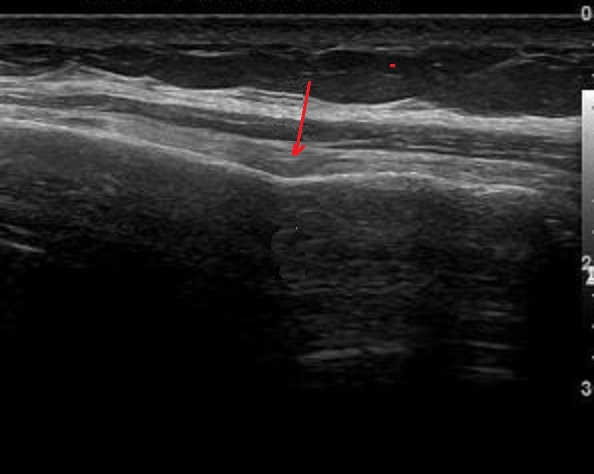

Aspect echographique d'une

fracture de cote du thorax avec lesion fraturaire de

de deplacement angulaire de cote . Oedeme

hypoechogene in situe de la partie molle ( fleche

rouge ) |